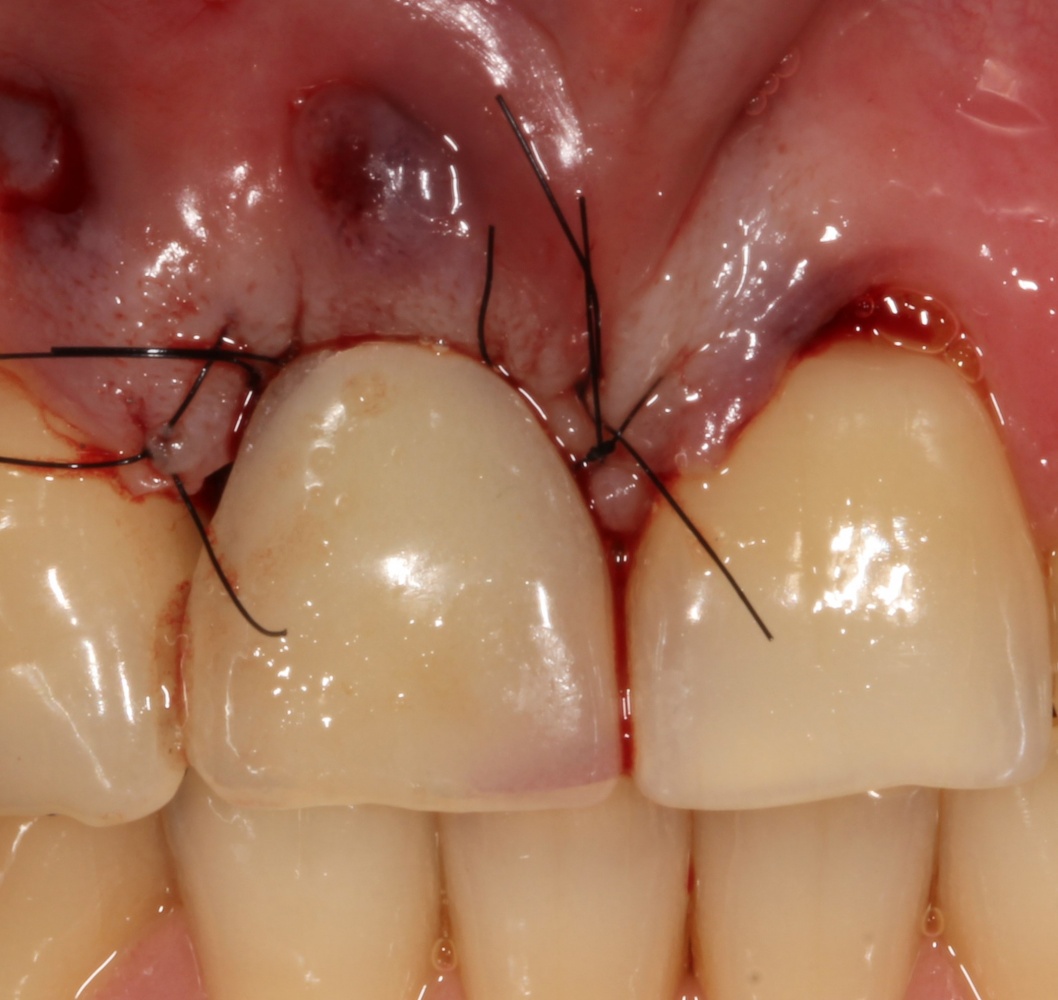

В данном случае мы планировали закончить этап немедленной установкой временной коронки, этим займется ортопед через полчаса после установки импланта. Пока же, я закрываю имплантат формирователем десны и накладываю швы:

Таким образом, вопрос об аугментации при немедленной имплантации решается, исходя из состояния вестибулярной стенки лунки, применение биоматериалов оправдано в случаях, если есть риски ее лизиса. Аналогичным образом принимается решение в области боковой группы зубов. Разве, что эстетический фактор тут учитывается, в большей степени, исходя из пожеланий пациента.

На имплантат ставим формирователь, ушиваем лунку. Напомню, что любой биоматериал должен быть герметично запечатан в ране (фактор успеха III). В противном случае, от него больше вреда, чем пользы: